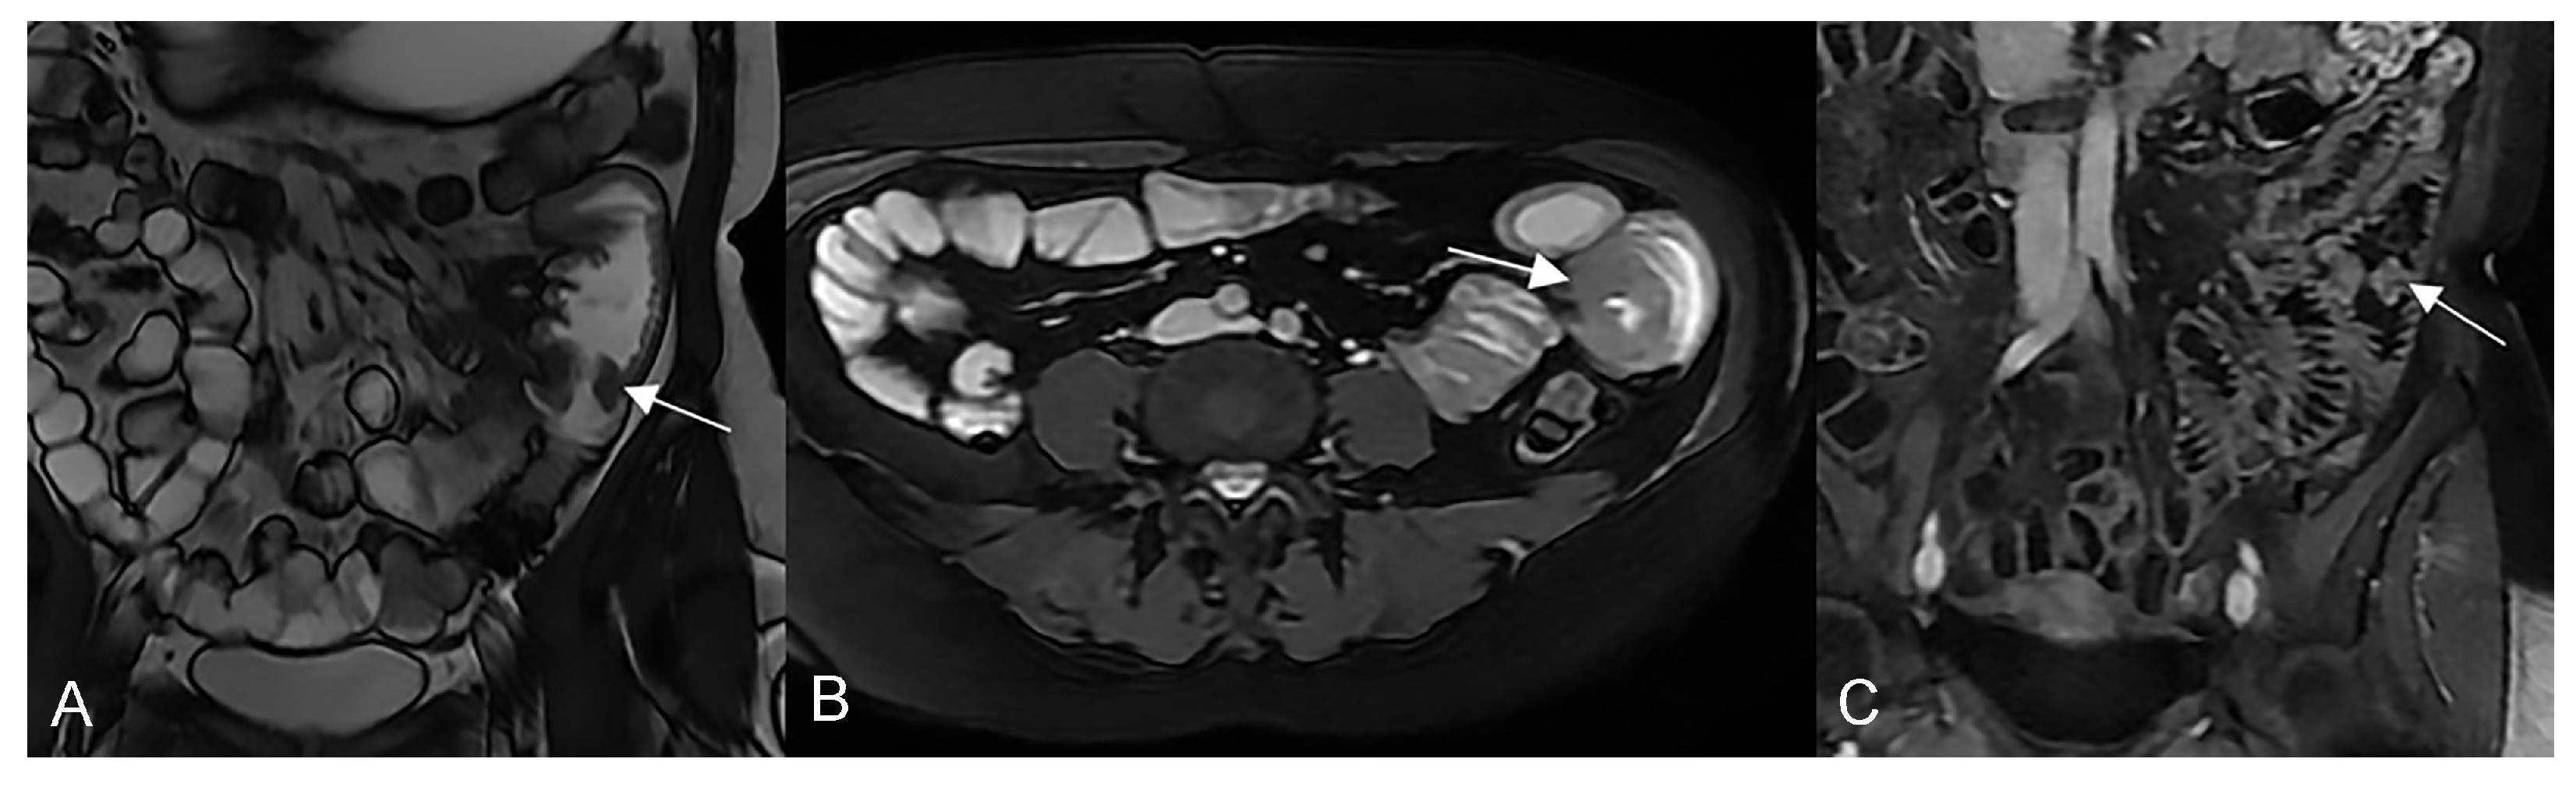

In the presence of small bowel thickening, degree, type, and extension of wall thickening must be indicated in the report. Depending on the wall thickness, thickening can be mild (<1 cm), moderate (>1 cm and <2 cm), or marked (>2 cm) [29] (Figure 16A).

Figure 16.

Degree of wall thickening and type of involvement along bowel circumference. (A) Axial T2-weighted image shows mild thickening (<1 cm) of an ileal loop in the pelvis (arrow). (B) Axial T2-weighted image shows moderate symmetric thickening (>1 cm and <2 cm) of a small bowel loop (black arrow), supported by edema of the submucosal layer. (C) Axial T2-weighted image shows marked asymmetric thickening (>2 cm) of an ileal loop in the pelvis (arrows); the other side of the bowel wall is less thick (arrowheads).

Thickening throughout the intestinal loop circumference might be eccentric (asymmetric) or circumferential (symmetric) depending on the type of involvement (Figure 16B,C) [29,30]. According to the length of the pathological bowel tract, thickening can be focal, segmental, or diffuse. Bowel thickening is defined as focal when the pathological tract is shorter than 5 cm in length (Figure 17A); segmental thickening refers to 6–40 cm in length of thickened small bowel (Figure 17B), while it is considered diffuse when a large amount of small bowel loops (>40 cm) is affected (Figure 17C) [29,30]. After contrast-medium injection, various patterns of wall enhancement can be described: stratified, white, and gray [30]. Contrast enhancement is classified as stratified when there is hyperintensity of the inner layer (muco-sa), hypointensity of the intermediate layer (submucosa), and hyperintensity of the outer layer (muscle and serosa layers); this is caused by mucosal hyperemia and submucosal edema. If stratified contrast enhancement is associated to fat deposits in the submucosal layer, it is called “fatty halo” sign [30,31].